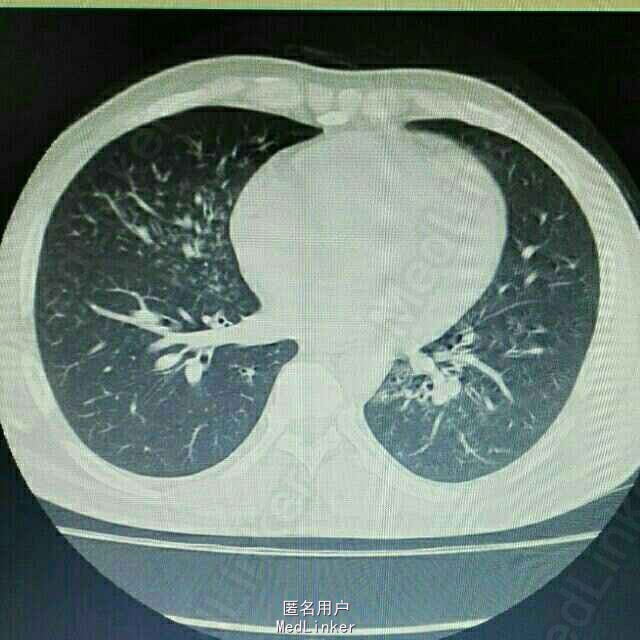

入院后行胸部CT检查,提示双肺弥漫性炎症,主要表现为间质性肺炎。

主诉:肾移植术后2月,发烧、咳嗽3天 病史:患者因尿毒症于2月前在我院行异体肾移植术,手术过程顺利,术后恢复良好,移植肾功能良好。服用FK506+MMF+Pred免疫抑制维持治疗。3天前无明显诱因出现发烧,最高体温39.0℃,伴咳嗽,无胸闷气促,无尿频尿急,无诉其他不适。

诊断:异体肾移植状态,肺部感染 治疗:入院后积极抗感染治疗,给予舒普深+赛美维+伏立康唑大包围抗感染治疗。并减用免疫抑制剂用量,加用丙球支持治疗,其余对症治疗。

随访:患者抗感染治疗2天后仍有发热,主要表现为早上发热,体温约38.3℃左右,给予对症降温治疗,请示上级医生指导停用所有口服免疫抑制剂,改为甲强龙40mgBid冲击治疗,维持原先抗感染治疗方案。 讨论:肾移植术后患者由于服用免疫抑制剂,为免疫缺陷人群,容易感染,其中以肺部感染最多见。肾移植术后的肺炎多为复杂性肺炎,该患者看起来像间质性肺炎,需要重点考虑巨细胞病毒(CMV)感染,这个往往有生命危险,所以要做好患者病情恶化的准备。